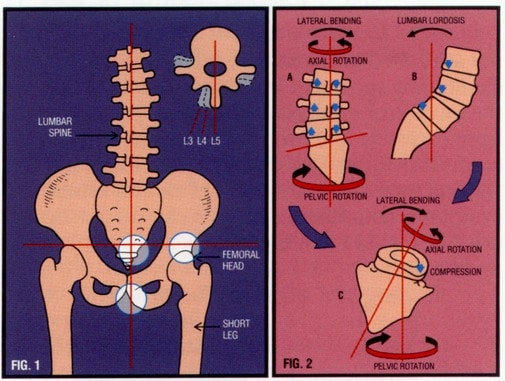

הסיבות לרוב הכאבים הללו וכן בהחלט גם לפריצות הדיסק, נעוצות בתפקוד לקוי של כריות הדיסק, חיישנים נוירולוגיים זעירים המפקחים על תנועת הגוף, השרירים, האגן ועצם העצה המהווים את בסיס הבניין של עמוד השדרה וחוליות הגב עליהן נשען הגוף.

9 מתוך 10 מטופלים חדשים מגיעים עם אגן הנוטה לצד מסוים ורגל אחת הנמשכת למעלה קצרה מדומה בין סנטימטר ועד אפילו חמישה סנטימטרים. הליכה זאת גורמת לעמוד השדרה להתפתל, להתעקם ולהפעיל עומסים לא שווים על כריות הדיסק. נטיית האגן איננה תוצאה של הכאב כי אם מקדימה אותו.

בבדיקות יציבה ועקמת בגילאי בית הספר היסודי וחטיבת הביניים נמצא רוב ניכר של בנים ובנות ההולכים עם אגן נוטה וארוכי רגליים לא שוות אך עדיין, ללא כאב.

עומסים אלו אשר לא מטופלים מניעתית ותחזוקתית על ידי הדוקטור לכירופרקטיקה, נשארים בלית ברירה או מחוסר ידיעה לטיפול על ידי רופאי המשפחה או המטופלים עצמם בעזרת משככי כאבים, פיזיוטרפיה וביקור תקופתי אצל אורטופד קופת החולים. בחלק המקרים משולבות גם זריקות בגב, בעמוד השדרה ופעולות פולשניות נוספות אך עדיין, המטופל נשאר עם אגן נטוי, הולך עקום ולא מאוזן והכאב חוזר וחוזר אם לא כל שבוע אז כל חודש או חצי שנה.